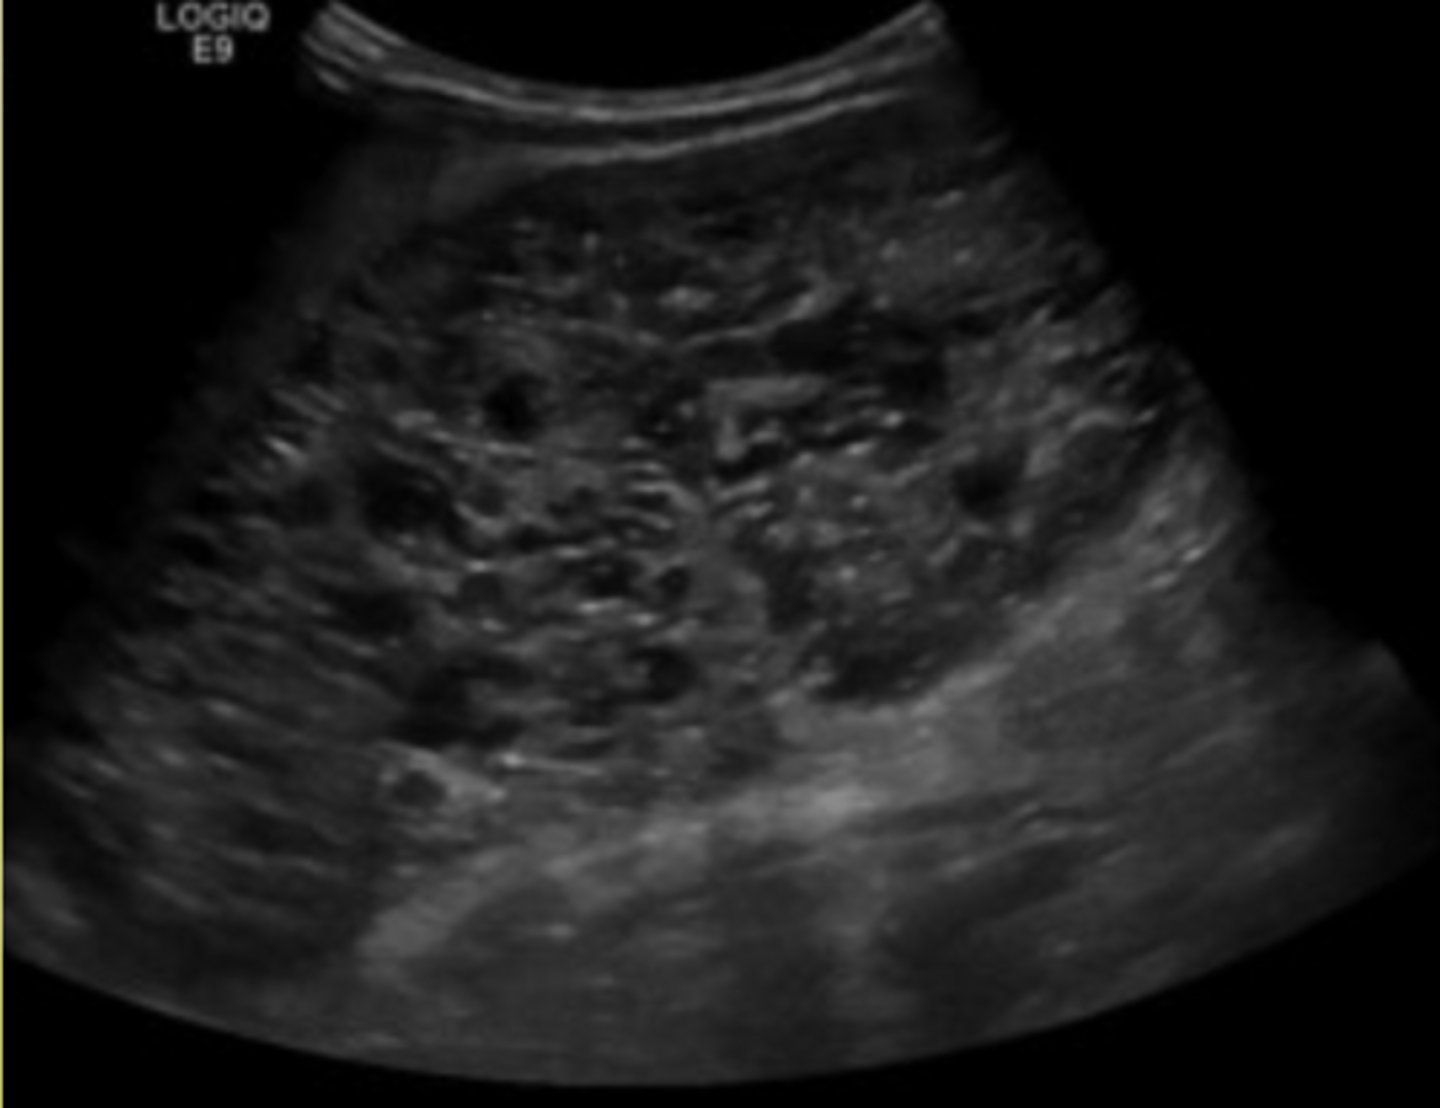

Polycystic Renal Disease

Multicystic Dysplastic Kidney is a ___ developmental disorder.

nonhereditary

Multicystic Dysplastic Kidney is usually ___ and if it is ___, it is typically ___.

unilateral, unilateral, asymptomatic

If Multicystic Dysplastic Kidney is bilateral, it is ___.

fatal

The kidney affected by Multicystic Dysplastic Kidney disease is usually ___.

nonfunctional

A kidney affected by Multicystic Dysplastic Kidney is ___ and made up of multiple ___ and little if any normal renal ___.

small, cysts, tissue

What is the most common source of palpable abdominal mass in infants?

Multicystic dysplastic kidney disease

If a patient has autosomal recessive polycystic kidney disease, what will the kidneys look like on ultrasound (Infantile)?

Large and echogenic due to many tiny cysts

If a patient has autosomal dominant polycystic kidney disease, what will that look like?

Kidneys become enlarged and are slowly replaced by large cysts

What is the most common inherited renal disorder?

Autosomal dominant polycystic kidney disease

When is autosomal dominant polycystic kidney disease usually diagnosed?

30s-40s

What are onset symptoms of autosomal dominant polycystic kidney disease?

Hypertension and renal failure

___% of patients with autosomal dominant polycystic kidney disease will also have ___ ___

50, liver cysts